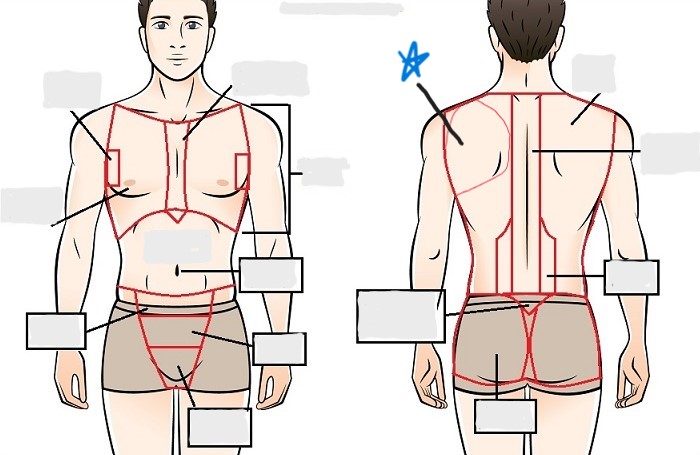

dorsal

scapular

vertebral

lumbar

sacral

gluteal

thoracic

sternal

mammary

axillary

abdominal

umbilical

pelvic

inguinal

pubic

perineal

appendicular

acromial

brachial

antecubital

olecranal

antebrachial

carpal

manus

coxal

femoral

patellar

popliteal

crural

sural

peroneal

calcaneal

plantar